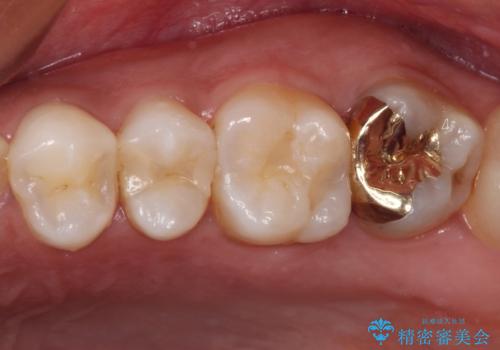

ゴールドインレーは銀歯のインレーやセラミックインレーと比べ、「技工操作の精度が高く、適合が著しく良い」というメリットがあります。特に上の奥歯は歯科医師の操作が行いにくいため、「適合の良さ」は再治療のリスクを防ぐ上でとても重要な要素となります。

上の奥歯は金属色が見えることもないため、審美的な問題は全くありません。

咬み心地はとても良好で、全く違和感がなく、患者様には大変満足していただきました。